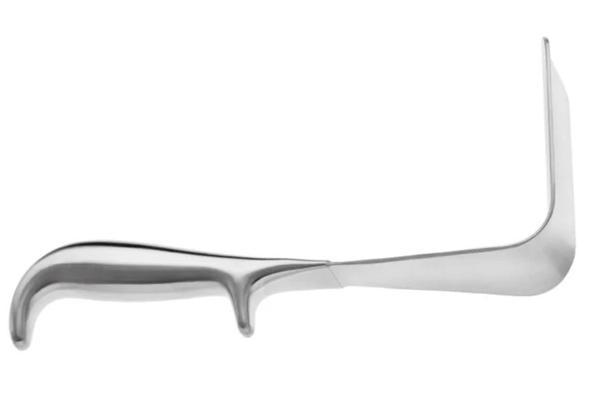

VALVE VAGINALE DE DOYEN 120 MM X 45 MM

Livré avec des lames biseautées qui permettent une insertion facile dans le vagin.

Comprend particulièrement des bords lisses avec une pointe émoussée qui aident à glisser à travers l’ouverture étroite.

Les courbes extérieures lisses de l’instrument protègent également les tissus mous des dommages.

A un design lisse et un poids léger qui ajoute au confort du chirurgien.

Fabriqué en acier inoxydable de qualité chirurgicale de la plus haute qualité avec finition satinée pour réduire l’éblouissement.

L’instrument peut être stérilisé et réutilisé.

| Dimension | 60 mm x 45 mm, 90 mm x 45 mm, 120 mm x 45 mm |